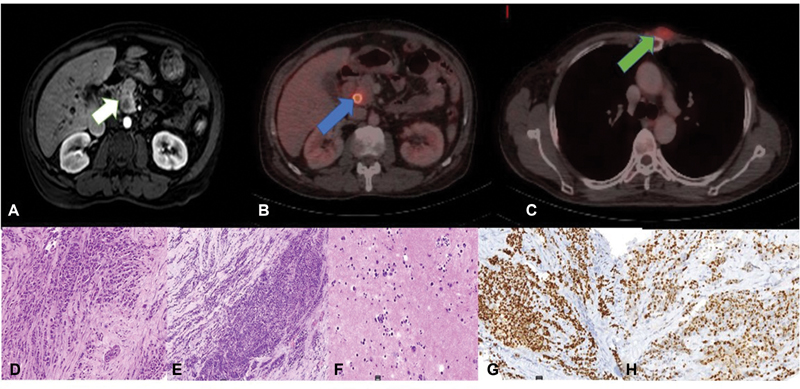

A 51-year-old man was diagnosed with left-sided breast cancer. He underwent a radical mastectomy, which on histopathology showed ILC and two positive axillary lymph nodes ([Supplementary Fig. S1A], available online only); estrogen receptor/progesterone receptor (ER/PR) was positive (Allred score—7/8 and 5/8, respectively) and HER 2 was negative ([Supplementary Fig. S1B–E], available online only). He received standard anthracycline and paclitaxel-based adjuvant chemotherapy. He also received locoregional radiation to chest wall and supraclavicular fossa. Patient was on maintenance tamoxifen when he presented with jaundice and anorexia after a disease-free interval of 2 years. On clinical examination, he had icterus and a 2 × 2 cm fixed chest wall lesion at the second costochondral junction. Biochemistry investigations revealed conjugated hyperbilirubinemia (total bilirubin—28 mg/dL, conjugated bilirubin—11mg/dL, serum glutamic-oxaloacetic transaminase—256IU/L, serum glutamic-pyruvate transaminase—109IU/L, alkaline phosphatase—249mU/mL) suggestive of obstructive jaundice. Serum CA-19.9 was within normal limits (24.35 U/mL). Abdominal ultrasound showed central intrahepatic biliary tract dilatation with a dilatated common bile duct (CBD) of 13 mm with an abrupt cutoff at the lower end. Magnetic resonance cholangiopancreatography was suggestive of a lesion in the head of pancreas measuring 9 × 8 mm involving the intrapancreatic CBD with upstream dilatation of suprapancreatic CBD, common hepatic duct, and intrahepatic biliary tract ([Fig. 1A]). A staging positron emission tomography-contrast-enhanced computed tomography showed increased uptake in an ill-defined soft tissue mass involving intrapancreatic bile duct and adjacent pancreatic parenchyma ([Fig. 1B]) (SUVmax—7.77) and a left parasternal soft tissue mass (SUVmax—5.88) ([Fig. 1C]). There was no other uptake on positron emission tomography in any other organ. A self-expandable metallic biliary stent was placed for recurrent cholangitis. Biopsy of chest wall lesion was recurrent ILC ([Fig. 1D]) and ER/PR was positive ([Fig. 1G, H]), consistent with that of the primary breast tumor. Radiological impression was that of an isolated pancreatic head mass. Two differentials of solitary pancreatic metastasis of lobular carcinoma and a second primary pancreatic head carcinoma were kept in mind. However, isolated pancreatic head metastasis from BC is extremely rare. In case of BRCA1 and BRCA2 mutation carrier incidence ratio for second pancreatic cancer reported to be 2.55 and 2.13, respectively.[7] On germline mutation analysis with hotspot common mutation testing with focused sequencing the patient had no pathogenic BRCA1 or 2 germline mutation. Staging laparoscopy was planned to be followed by a pancreaticoduodenectomy if resectable and localized pancreatic lesion along with wide excision of chest wall recurrence. However, on laparoscopy, he was found to have multiple subcentimetric peritoneal nodules with mild ascites with peritoneal carcinomatosis index >10. Multiple peritoneal biopsies were taken and ascitic fluid was sent for cytology. A decision to defer definitive treatment was made awaiting final histopathology report of the intra-abdominal biopsies. The histopathology of peritoneal nodule ([Fig. 1E]) and cytopathology of ascitic fluid cytology and cell block ([Fig. 1F]) proved the intra-abdominal disease to be recurrence and pancreatic metastasis of lobular carcinoma rather than a second primary. Patient was deemed to have metastatic BC and started on next line of hormonal therapy, that is, luteinizing hormone-releasing hormone (LHRH) agonist and aromatase inhibitor. The patient further progressed after 3 months and was started on weekly paclitaxel. He finally succumbed to disease after 5 months.

| Figure. 1 Imaging and histopathological features of recurrent lobular carcinoma: (A) Post-contrast magnetic resonance image shows a peripherally enhancing mass in the head of pancreas with moderate upstream intrahepatic biliary radical dilatation (white arrow). (B) Fused positron emission tomography computed tomography (PET/CT) shows fluorodeoxyglucose avid lesion at the head of pancreas (SUV max 7.77) with stent in situ (blue arrow). (C) Fused PET/CT shows the chest wall recurrence (SUV max 5.88) (green arrow). (D–F) Biopsy from chest wall recurrence, peritoneal nodule biopsy and peritoneal fluid cytology (hematoxylin and eosin, 20x). (G, H) Immunohistochemical markers of recurrent chest wall lesion diffuse staining for estrogen receptor and progesterone receptor.

| Figure. 1 Imaging and histopathological features of recurrent lobular carcinoma: (A) Post-contrast magnetic resonance image shows a peripherally enhancing mass in the head of pancreas with moderate upstream intrahepatic biliary radical dilatation (white arrow). (B) Fused positron emission tomography computed tomography (PET/CT) shows fluorodeoxyglucose avid lesion at the head of pancreas (SUV max 7.77) with stent in situ (blue arrow). (C) Fused PET/CT shows the chest wall recurrence (SUV max 5.88) (green arrow). (D–F) Biopsy from chest wall recurrence, peritoneal nodule biopsy and peritoneal fluid cytology (hematoxylin and eosin, 20x). (G, H) Immunohistochemical markers of recurrent chest wall lesion diffuse staining for estrogen receptor and progesterone receptor.